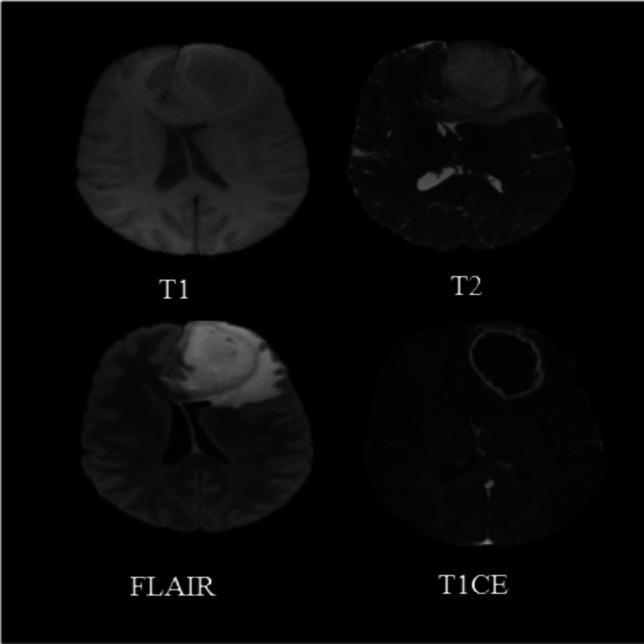

Deep learning classification of MGMT status of glioblastomas using multiparametric MRI with a novel domain knowledge augmented mask fusion approach.使用具有新型领域知识增强掩码融合方法的多参数MRI对胶质母细胞瘤的MGMT状态进行深度学习分类。

Sci Rep. 2025 Jan 25;15(1):3273. doi: 10.1038/s41598-025-87803-0.